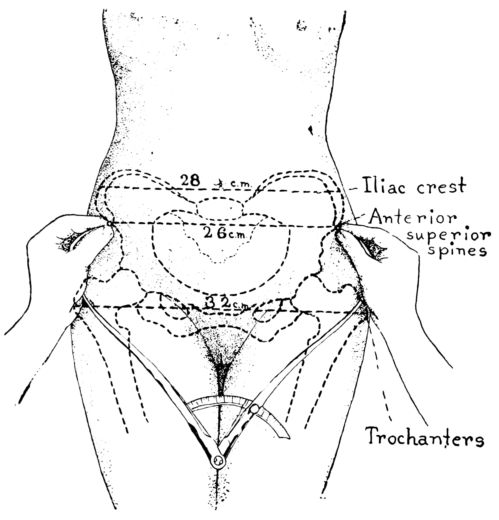

According to a common system of mensuration, the first external measurement is the inter-spinous, the distance between the anterior-superior spines, those bony points which are uppermost as the patient lies on her back. This distance is normally 26 centimetres. (Fig. 6.)

The second measurement is the inter-crestal, or the distance between the iliac crests, and is normally 28 centimetres.

Baudelocque’s diameter is the third measurement and is taken with the patient lying on her side. (Fig. 7.) It is the distance from the top of the symphysis to a depression just below the last lumbar vertebra. This depression is easily located as it also marks the upper angle of a space just above the buttocks, which in normal pelves is quadrilateral. In malformed pelves this quadrangle may be so misshapen as to become almost a triangle with the apex directed either up or down. This dimension 26is sometimes called the external conjugate and ordinarily measures 21 centimetres.

The fourth measurement is the distance between the great trochanters, or heads of the femora, and normally is 32 centimetres.

Fig. 6.—Diagram showing method of measuring distances between iliac crests and spines and the trochanters.